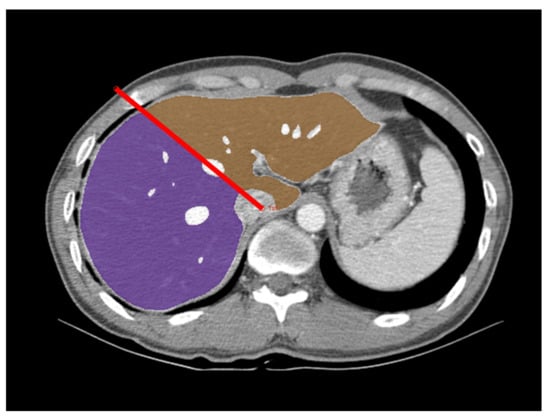

2.3. Graft Volume Measurement Using a Deep Learning Algorithm

3.2. Liver Segmentation and Graft Volume Estimation Using DLA